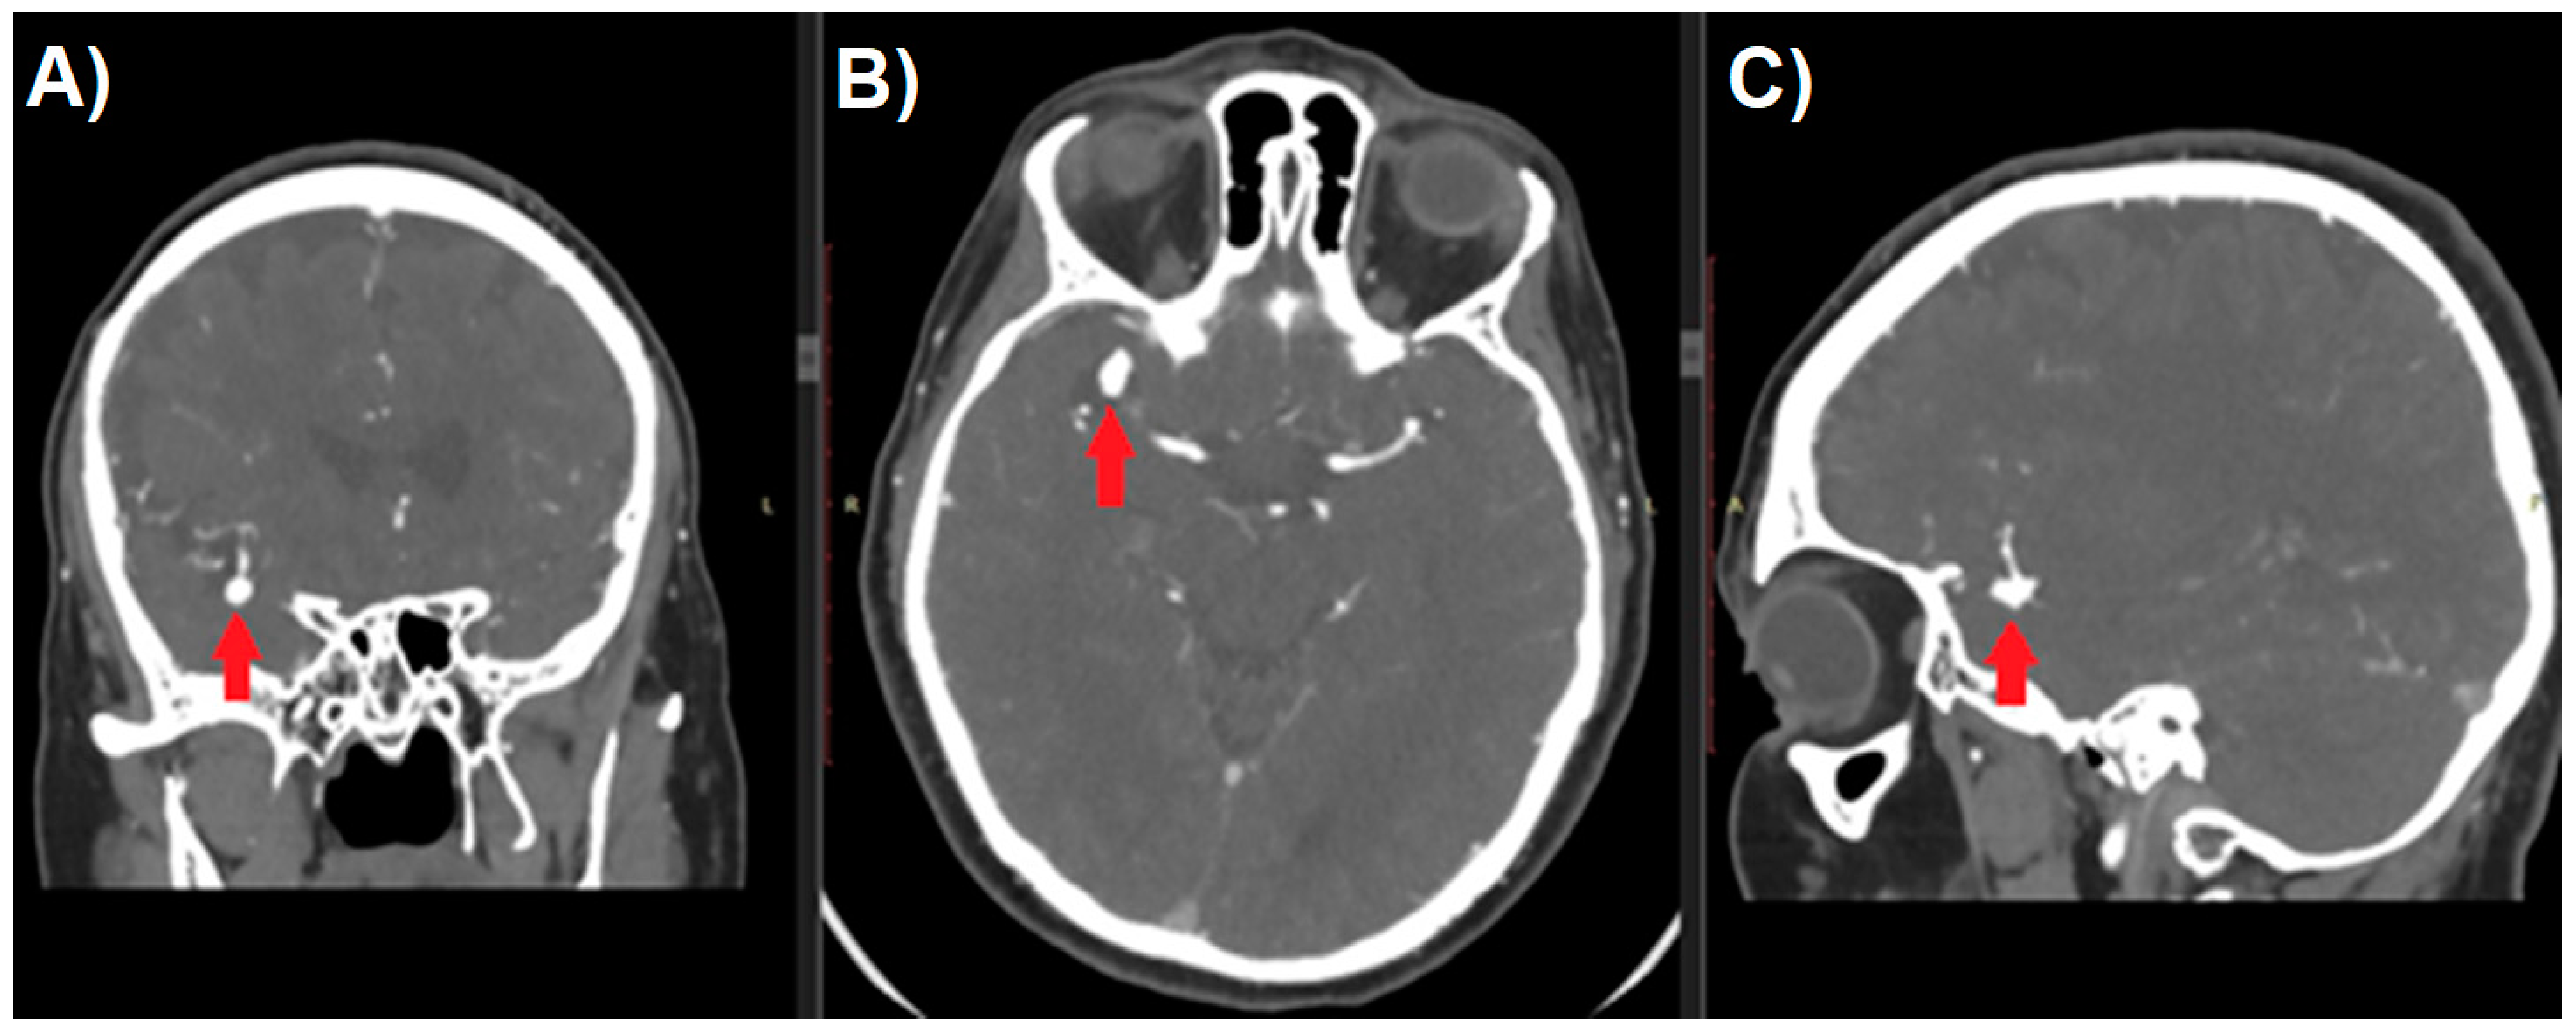

Aneurysm management starts with a thorough analysis of the anatomy. Raw image data from CT-angiography create axial slices through the examined part of the anatomy and can be converted to create sagittal and coronal projections (Figure 1). Unfortunately, because of the two-dimensional nature of such images, they usually fail to provide an accurate perception of treated pathology. Most DICOM viewers allow to perform the reconstructions of such images to create more like-3D images. Maximum Intensity Projection (MIP) and shaded surface display volume rendering techniques (SS-VRT) are mostly utilized. As it is shown in Figure 2, the first one consists of projecting several slices with the highest attenuation value on every view throughout the volume onto a 2D image [8]. Considering vascular diseases, this technique allows to trace the course of vessels neighboring to the aneurysm, thus producing the opportunity to visualize the pathology in a way accurate enough for preoperative planning.

Figure 1.

Multi-planar reconstruction of Computed Tomography Angiography study of patient with cerebral aneurysm (red arrow). Digital Imaging and Communications in Medicine (DICOM) image in (A) coronal, (B) axial, and (C) sagittal plane.